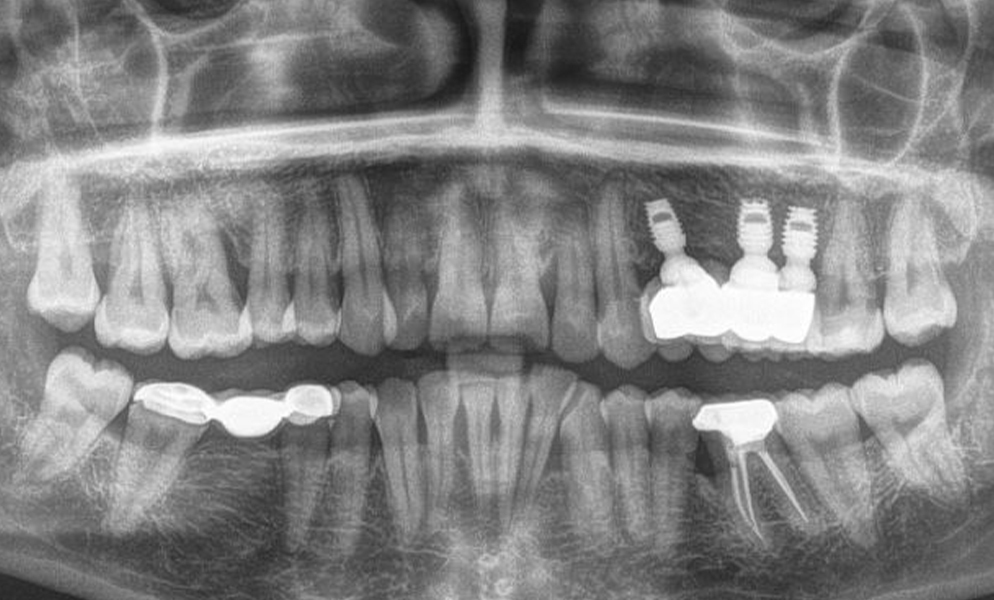

| Before | After |

![]() |

| Single posterior tooth missing space restored with a 4x6 mm short dental implant (Bicon, USA) to avoid sinus lift and bone graft procedures | |